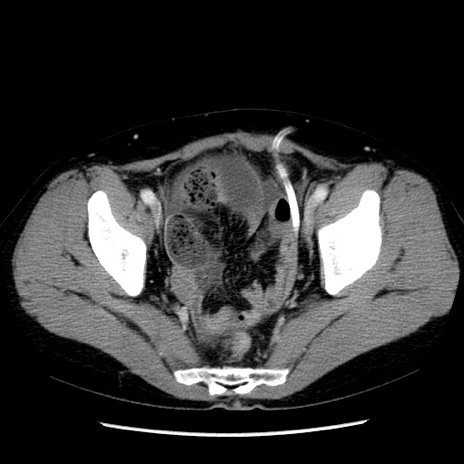

矢状断像